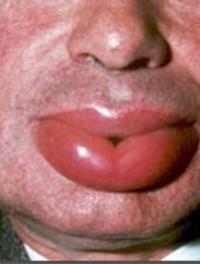

Le syndrome périodique associé à la cryopyrine (SPAC ou CAPS en anglais) regroupe plusieurs affections génétiques rares caractérisées [...]